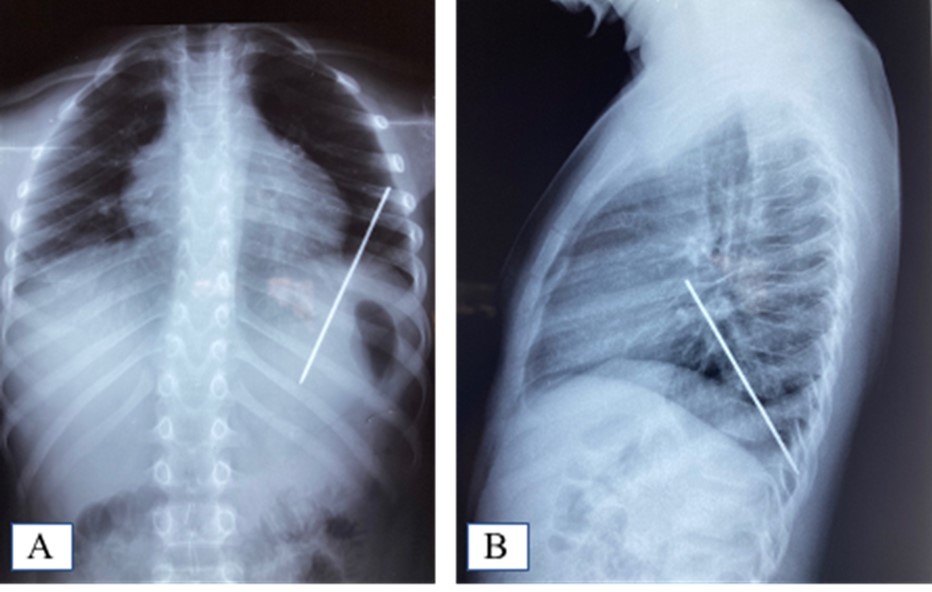

AD, aged 10, with no particular pathological history, was referred to us for the management of a post-traumatic intrapulmonary foreign body. The traumatism would have occurred one month earlier, during a playful accident. He would have received from his brother, at the level of the left hemithorax, a blow with the metal tail of a comb. The latter would then have been torn off by the child but without the tail. This would have caused a minimal wound, associated with an intense chest pain, without dyspnea, or cough, justifying local care and treatment with analgesics. The incident was withheld from parents. On admission, there was a punctiform scar in the 2nd left intercostal space, about 5 cm from the sternal border. The pulmonary fields were free. The rest of the exam was normal. The biological results were normal. A first chest x-ray showed a metal rod, oblique downwards, backwards and inwards, going from the 5th to the 11th left costal arch (Figure 1). The computed tomography scan of the chest showed the metal rod in the lung parenchyma. It was approximately 105 mm long and stayed away from the heart and the great vessels. There was no pulmonary parenchymal abnormality, pleural effusion or obvious bone lesion (Figure 2). Two subsequent X-rays showed its migration downwards, inwards and backwards with an upper pole sitting opposite the posterior arch of the 8th rib. A left posterolateral thoracotomy approach allowed the removal of the metal rod lodged in the lower lobe of the lung (Figure 3). The postoperative period was unremarkable. The ablation of the drains was carried out on the5th postoperative day. The patient was discharged on the 8th day. Reviewed in the6th postoperative month, his examination was normal.

Figure 1.A. Frontal chest X-ray showing the foreign body; B: Foreign body sparing the diaphragm on the lateral chest X-ray